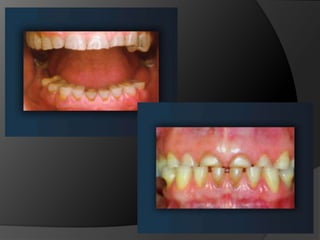

El análisis para seleccionar la ubicación de la línea de terminación se enfoca en 2 componentes:Estética vs HigieneExtensión mínima dentro del surco gingivalDisimular la zona de asentamientoFacilitar la higiene del pacienteNecesidad de aumentar la retención y estabilidadLínea de Sonrisa

El análisis paraseleccionar la ubicación de la línea de terminación se enfoca en 2 componentes:Estética vs HigieneExtensión mínima dentro del surco gingivalDisimular la zona de asentamientoFacilitar la higiene del pacienteNecesidad de aumentar la retención y estabilidadLínea de Sonrisa